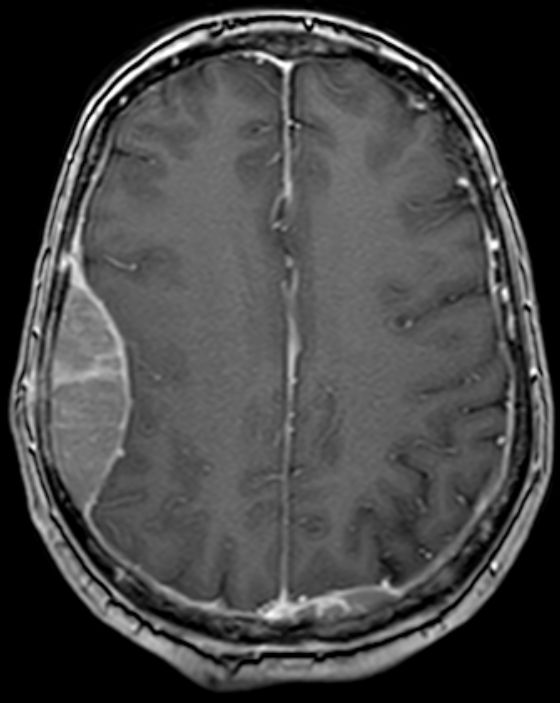

| Extradurale RF |

Gleiche Patientin mit einer intracraniellen, extraduralen Raumforderung. Die

Kontrastmittelaufnahme spricht für einen soliden tumorösen Prozess. ![]() | |||